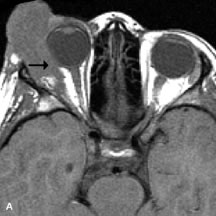

PATIENT PREPARATION Before MRI is performed, patients must be screened and prepared to avoid the potential hazards associated with the strong magnetic field. Patients who have ferrous aneurysm clips or cardiac pacemakers, who depend on life-support equipment, or who retain a possible metallic intraocular foreign body are not candidates for this imaging modality. MRI cannot be performed on obese patients who cannot fit into the bore of the magnet. Patients who are claustrophobic may not tolerate a prolonged period of study within the confines of the magnet, whereas others might do well if given a mild sedative. All worn metallic objects (e.g., necklaces, watches) should be taken off, credit cards set aside, and eye makeup removed before entering the room containing the magnet.5,20,34,35,36 NORMAL ORBITAL ANATOMY T1-weighted images provide the best anatomic details of the orbit because they display superior contrast resolution between normal structures (see Fig. 8). The vitreous has a long T1, resulting in an intermediate signal similar to brain, whereas the crystalline lens and sclera appear dark because of a longer T1 and short T2. The extraocular muscles, like all skeletal muscles, demonstrate a moderately long T1 and short T2 and highly contrast with the intense signal of the surrounding orbital fat (adipose tissue has an extremely short T1). The lacrimal glands appear as mottled areas of reduced intensity of the signal from the orbital fat in the lacrimal fossa. The optic nerves are seen with the same signal intensity as brain white matter and are hypointense relative to the orbital fat because their Tl is longer than the Tl of fat but shorter than the Tl of water. Cortical bone is not well delineated because it contains little free water, yielding minimal signal in MRI, and thus appears dark on all pulse sequences. This feature explains why MR images of the orbital apex and intracanalicular portion of the optic nerves are superior to comparable CT scans. Partial volume averaging of the bones in these regions obscures soft tissue details on CT images, whereas MRI reveals the signals only from the soft tissue structures with no cortical bone input. Bone marrow, on the other hand, is seen as a relatively intense signal because of its high fat content (see Fig. 8).37,38 T2-weighted pulse sequences are not ideal for imaging normal anatomy; however, they are particularly useful in revealing pathologic conditions (see Fig. 9). T2-weighted studies are most easily recognized by a bright vitreous signal. ORBITAL DISEASES Vascular Lesions Cavernous hemangiomas appear as well-circumscribed, smooth, usually intraconal masses that are isointense to muscle on T1-weighted images and hyperintense on T2-weighted images (Fig. 12). Patchy early enhancement is typically followed by diffuse, more homogeneous enhancement.39 The internal architecture of the mass, including septation and internal vasculature, may often be appreciated with high-quality orbital imaging.40 Lymphangiomas consist of ectatic vascular channels within a connective tissue stoma with varying degrees of lymphoid cellularity. On MRI, these tumors are typically poorly circumscribed, multicompartmental, and heterogeneous, often showing cystic dilations with fluid levels (Fig. 13). The signal characteristics within lymphangiomas vary considerably, reflecting cystic and solid components and the varying paramagnetic characteristics of blood at different stages of degradation.40–42 Acute hemorrhage appears hypointense on both T1- and T2-weighted formats. Methemoglobin present in subacute hemorrhage (3 to 14 days) leads to hyperintense signal on both T1- and T2-weighted images.41 A small percentage of lymphangiomas appear radiologically indistinct from orbital cavernous hemangiomas.43 Orbital varices are venous malformations that expand with increased systemic venous pressure, such as with Valsalva maneuvers. Because rapid acquisition of images during a Valsalva maneuver is important in imaging such a lesion, conventional or spiral CT is currently the modality of choice.44 MRI is an excellent modality for demonstrating enlargement of the cavernous sinus and dilation of the superior ophthalmic vein in patients with high-flow carotid-cavernous fistulas (Fig. 14).37MRA may be helpful in the evaluation of the venous outflow pattern. The rapidly flowing blood in these vascular structures carries the excited protons out of the section before they can be imaged, resulting in their dark appearance.5 In low-flow dural arteriovenous malformations, MRA may help define the arterial feeding vessels.45 Neural Lesions MRI is more effective than CT in delineating the intracranial optic nerves, chiasm, and optic tracts and, for this reason, is the preferred imaging modality in the evaluation of optic nerve disorders. The spatial relationships and image contrast of the orbital tissues with intraorbital optic nerve tumors is comparable between the two imaging modalities. The normal nerve is isointense to brain and appears enlarged and kinked owing to infiltration of an optic nerve glioma on T1-weighted images. Gliomas appear hyperintense on T2-weighted images and may be heterogeneous owing to cystic areas within the tumor. Contrast enhancement is variable.46 Intraorbital and intracranial optic nerve sheath meningiomas are usually isointense to cortical gray matter on Tl-weighted images and remain isointense on proton density studies (Fig. 15). Gd-DTPA is useful in delineating the intracranial extension of optic nerve meningiomas.7,47 The hyperostosis of bone and calcification associated with meningiomas are not demonstrated as well on MRI studies as on CT scans.20,37 Gd-DTPA–enhanced MRI also appears promising in the study of the permeability of the blood–brain barrier in selected optic neuropathies.22,48 MRI may reveal an enlarged optic nerve and some degree of contrast enhancement in cases of optic neuritis.49 Muscle Disorders Extraocular muscle enlargement in patients with thyroid-associated orbitopathy is demonstrated equally well with CT and MRI studies. However, the superior tissue contrast on MR images reveals better details of the relationships of the optic nerve to the thickened muscles at the orbital apex (Fig. 16).50 In addition, MRI may be able to differentiate between muscles that are enlarged as a result of edema and active inflammation and those enlarged because of fibrosis by their T2 relaxation times.21 Quantitative MRI was not found to be accurate in predicting the success of low-dose orbital irradiation.51 However, a muscular index relating the diameters of the rectus muscles to the bony orbital dimensions was useful in predicting optic nerve compression.52 MRI is also effective in imaging orbital tumors of mesenchymal origin, such as rhabdomyosarcoma, particularly in the assessment of extension into the anterior and middle cranial fossae (Fig. 17).37 The lack of any pathognomonic radiologic features necessitates rapid orbital biopsy when rhabdomyosarcoma is suspected. Osseous Lesions In general, CT is the imaging modality of choice when details of quantity and quality of bone are needed; however, abnormalities of bones can be detected indirectly by MRI. Cortical bone appears black (signal void) on MR images because of its low proton density and free-water content. The absence or discontinuity of the signal void of the orbital walls may represent bony destruction or fracture. Hyperostosis associated with prostate metastases or meningioma is visualized as areas of black smudging.50,53 Diseases in which the bone is replaced by pathologic tissues with a high free-water content, such as fibrous dysplasia, are well demonstrated on MRI. An intermediate signal intensity on T1-weighted images and hypointense signal on T2-weighted images is representative of fibrous dysplasia. Enhancement on post–Gd-DTPA MR scans is seen and is more evident in areas that are less mineralized.54 Cystic Lesions Dermoid cysts appear as rounded, well-defined lesions typically contiguous with an orbital bony suture. The high-intensity signal on T1-weighted images is attributed to the sebaceous-produced lipid contents (Fig. 18).31,50 Mucoceles may demonstrate a hypointense or hyperintense signal on MR images, depending on the concentration of proteinaceous or inflammatory fluid components. The integrity of the bony walls of the expanded sinus cavities cannot be assessed on MR as well as by CT.37,50,55,56 A high-signal intensity on Tl- and T2-weighted images is characteristic of orbital chronic hematic cysts because of the blood-breakdown products within the cysts.57 Trauma Although soft tissue relationships are usually better demonstrated on MRI, the evaluation of craniofacial bony trauma is preferable with CT. For example, prolapse of orbital fat through a fracture site and hemorrhage of adjacent tissues are demonstrated in an MR image, but the actual fractured bone is not imaged. Three-dimensional MRI of the orbit in subacute trauma has been described,58 although its precise role is not currently established. MRI has been suggested to be superior to CT in detecting intraorbital wooden foreign bodies.59,60 In a series of penetrating orbital injuries with organic foreign bodies, however, MRI was able to identify the foreign body in only four of seven cases.61 With an in vitro model for wood foreign body, McGuckin and colleagues concluded that CT was the imaging modality of choice.62 A careful history and, in selected cases, plain films to rule out a metallic foreign body are crucial before MRI is considered in patients with periocular trauma. MRI is particularly helpful in the detection and characterization of subperiosteal hematomas of the orbit (Fig. 19). They are most commonly seen in the subperiosteal space of the superior orbit as well-defined masses following a traumatic injury. The signal intensity varies depending on the acute, subacute, or chronic nature of the hematoma, based on the stage of blood degradation. Fresh hemorrhages are hypointense on T1-weighted images and hyperintense on T2 images. Hematomas that are 1 to 7 days old are hypointense on both T1- and T2-weighted images. T1-weighted images of hematomas more than a week old are hyperintense due to the oxidation of deoxyhemoglobin to methemoglobin, whereas the T2 images remain hypointense.63 Metastatic Tumors Breast carcinoma metastatic to the orbit has been demonstrated to be hypointense to the surrounding orbital fat on T1-weighted studies and hyperintense on T2-weighted images and has an affinity to the extraocular muscles (Fig. 20).50,64 The MRI characteristics of prostate carcinoma metastatic to the orbit have been described as involving the greater and lesser wing of the sphenoid, orbital roof, and optic canal. Diffuse bone hypertrophy with isointense or slightly hyperintense tissue on T1-weighted images represents the osteoblastic carcinomatous bone infiltration. Contrast enhancement is variable on T1-weighted and fat-suppressed images.65 Most other metastatic tumors also have a lower intensity signal on T1-weighted images and appear to displace or infiltrate normal orbital structures; however, their signal characteristics are variable on T2-weighted MR images.66 Many metastatic tumors demonstrate bright contrast enhancement with Gd-DTPA. Infectious Disorders MRI findings of preseptal and orbital cellulitis typically include increased signal intensities on T2-weighted images of the eyelids and orbital fat, respectively, due to the increased water content of the tissues. Since most cases of bacterial orbital cellulitis are associated with paranasal sinusitis, hyperintense signals of the affected sinuses may also be found on T2-weighted images as well as enhancement of polyps and granulation tissue on postgadolinium T1-weighted MR images. Subperiosteal abscess formation may occur due to contiguous spread of infection from the paranasal sinuses and appear on MRI as an area of intermediate signal on T1-weighted and proton-weighted MR images. The abscess may appear slightly hyperintense compared with muscle on T2-weighted scans with the necrotic contents having the greatest intensity.67 MRI and MRV are more sensitive than CT in revealing cavernous sinus thrombosis. Engorgement of the cavernous sinus, extraocular muscles, and ophthalmic veins is seen with hyperintensity of the thrombosed sinuses evident on all pulse sequences. The enlarged, thrombosed superior ophthalmic vein appears less hypointense than the normal contralateral ophthalmic vein, and hyperintensity within the lumen of the vessel may be seen on T1- and T2-weighted MR images.68 Inflammatory and Lymphoproliferative Lesions Inflammatory conditions of the orbit, both idiopathic (inflammatory pseudotumor) and those of known causes, have been found to be hypointense to fat and isointense to muscle on Tl-weighted studies and isointense or slightly hyperintense to fat on T2-weighted images (Fig. 21).50,64,69 The more fibrous or sclerosing varieties have less signal intensity on T2-weighted images. Marked enhancement is seen in pseudotumor infiltrates after gadolinium administration.70 The same signal characteristics are demonstrated in patients with Tolosa-Hunt syndrome, with mass lesions seen in the cavernous sinuses and orbital apices.71 Lymphomas have MRI characteristics similar to those of inflammatory lesions in that they are hypointense to fat and isointense to muscle on T1-weighted images (Fig. 22). They may appear hyperintense to fat on T2-weighted images, perhaps owing to less fibrosis than that seen in orbital inflammatory pseudotumor, although this is not a consistent finding.31,50,66 Lymphoid tumors typically enhance moderately after contrast injection. Unfortunately, studies have shown that tumor density and homogeneity are similar between inflammatory and malignant orbital infiltrates, and MRI cannot differentiate these lesions.72,73 Lacrimal Gland Tumors Lacrimal gland lesions present special problems in diagnosis and management. Pleomorphic adenoma (benign mixed tumor) should not be biopsied, but rather excised in toto. On the other hand, for lymphoma and inflammatory infiltrates, incisional biopsy is more appropriate than complete excision of the lacrimal gland. Thus, preoperative clinical and radiologic evaluation are especially crucial in planning appropriate surgical management. Pleomorphic adenomas demonstrate long T1 and T2 signal characteristics. They may show heterogeneity on T2-weighted images74 and moderate to marked enhancement with contrast.75 Signal characteristics of adenoid cystic carcinoma include hypointensity to fat on T1-weighted images, hyperintensity to fat with increased T2 weighting, and isointensity to fat on proton density-weighted studies (Fig. 23).31,75 Secondary bony alterations of the lacrimal fossa associated with lacrimal gland tumors, such as remodeling (benign mixed tumor) or destruction (adenoid cystic carcinoma), are seen indirectly on MR images; however, bone windows on CT scans provide better delineation of these changes. In contrast to the round or globular appearance of benign or malignant epithelial tumors of the lacrimal gland, lymphoproliferative tumors usually appear to be molding or draping onto the globe and the surrounding bony orbit. LACRIMAL DRAINAGE SYSTEM DISORDERS MRI with surface coils provides excellent spatial resolution and tissue-specific signal intensities of the lacrimal drainage system. These parameters have been found useful to more accurately demonstrate the extent of lesions in the lacrimal sac and differentiate long-standing mucoceles from solid tumors than CT.76 Physiologic studies in patients with tearing disorders now include MR dacryocystography, in which Gd-DTPA is either placed topically in the conjunctival fornix or injected by cannulation into the lacrimal sac. They provide a detailed morphologic and functional analysis of the lacrimal excretory system; however, they are no more sensitive than digital-subtraction dacryocystography or CT dacryocystography.77–79 INTRAOCULAR TUMORS On MRI, uveal melanomas have a typical appearance that helps to differentiate them from other primary and secondary intraocular tumors as well as choroidal detachments. Pigmented melanomas are hyperintense on Tl-weighted images, hypointense on T2-weighted studies, and hyperintense on proton density–weighted examinations (Fig. 24).30,31,50,80–82 These signal characteristics have been attributed to the paramagnetic properties of melanin because of stable free radicals that shorten the T1 and T2 relaxation times. Moderate enhancement is seen on postgadolinium T2-weighted images. Gadolinium-enhanced T1-weighted images are particularly sensitive in detecting choroidal melanomas.83 MRI may be less sensitive in detecting extrascleral extension of tumor than echography performed by an experienced ultrasonographer.84 Tumors metastatic to the choroid are hyperintense on T1- and T2-weighted images.24 The signal characteristics, however, may be similar to those seen with choroidal melanoma. Choroidal hemangiomas, on the other hand, have an intermediate signal on T1-weighted sequences and become hyperintense on T2-weighted images50 as well as proton density–weighted images.81 Retinoblastomas display moderate signal intensity on T1-weighted studies and a low signal on T2-weighted images.31,80,85 Calcification can be easily detected by CT and ocular ultrasonography but is not imaged by MRI.25,50 The presence of optic nerve involvement is best evaluated by MRI. ACQUIRED ANOPHTHALMIA When an eye is removed owing to tumor or trauma, an implant is typically placed in the intraconal space. MRI may be useful in defining the size, shape, and position of such orbital implants.86 Porous hydroxyapatite or polyethylene implants are preferred by many surgeons performing enucleation or evisceration. A porous implant offers the possibility of supporting a motility coupling peg to increase the movement of the overlying prosthesis. MRI with contrast is used by some surgeons to evaluate the degree of fibrovascular ingrowth in hydroxyapatite87 and porous polyethylene88 implants prior to motility peg placement. |